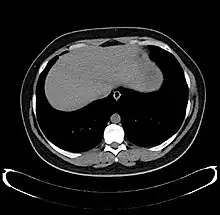

The diagnosis of liver disease is made by liver function tests, groups of blood tests, that can readily show the extent of liver damage. If infection is suspected, then other serological tests will be carried out. A physical examination of the liver can only reveal its size and any tenderness, and some form of imaging such as an ultrasound or CT scan may also be needed.

Axial CT image showing anomalous hepatic veins coursing on the liver's subcapsular anterior surface[66]

A CT scan in which the liver and portal vein are shown